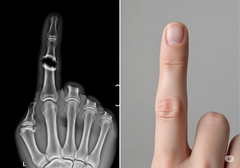

La fusión espinal es un procedimiento habitual para tratar el dolor de espalda debilitante uniendo dos o más vértebras, pero puede tener un alto índice de fracaso. Los tratamientos actuales suelen basarse en injertos óseos o potentes factores de crecimiento que a veces pueden provocar complicaciones, como la formación incontrolada de hueso fuera de la zona objetivo.

El enfoque de Bone Biologics se centra en la proteína NELL-1, un factor de crecimiento que interviene de forma natural en el desarrollo óseo. Los estudios preclínicos han demostrado que la NELL-1 es excepcionalmente capaz de estimular un crecimiento óseo robusto precisamente donde se necesita, al tiempo que inhibe la formación de células grasas, un problema común con otros biológicos. Esta acción dirigida podría dar lugar a fusiones más fiables y menos complicaciones.